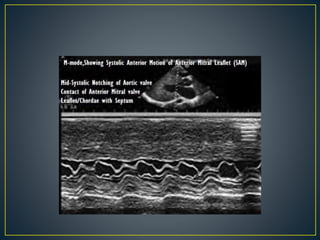

• Produced by SAM of mitral valve

• Explanations for the SAM of the mitral valve

1. Mitral valve is drawn toward the septum

because of the lower pressure that occurs as

blood is ejected at high velocity through a

narrowed outflow tract (Venturi effect)

2. Mitral valve is pulled against the septum by

contraction of the papillary muscles, which

occurs because of the valve's abnormal location

and septal hypertrophy altering the orientation

of the papillary muscles

3. Hydrodynamic “drag” or the “pushing” force of

flow